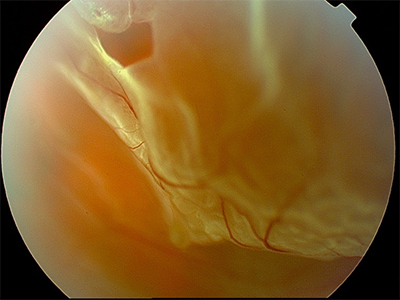

ophtavalmy.frFond D’oeil_Décollement Rétine Supérieur Avec Déchirure Rétinienne

ophtavalmy.frFond D’oeil_Décollement Rétine Supérieur Avec Déchirure Rétinienne